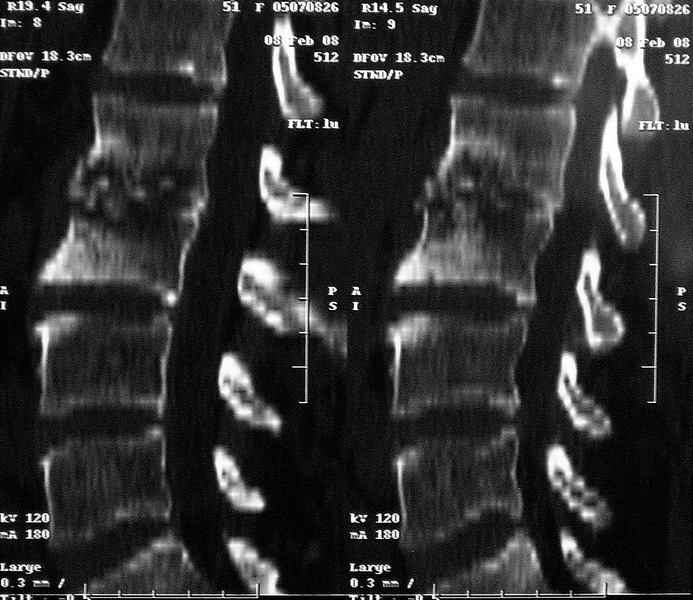

Отправляю MRI в динамике, снятые с пленки на фотоаппарат.

|

MRI через три недели

По данным представленных КТ и МРТ у больной имеется достаточно выраженная степень деструкции тел позвонков (около 30% общей костной массы тела позвонка), что определяет высокий риск возникновения патогических переломов и появления локальной кифотической деформации на этом уровне.

Судя по снимкам похоже идет речь о спинальном остеомиелите для диф диагноза стоит провести черезкожную пункционную биопсию(с помощью КТ)